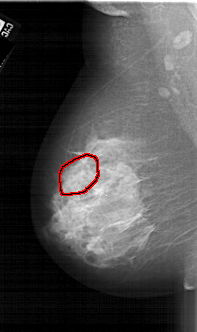

A_1667_1.LEFT_CC

FILE: A_1667_1.LEFT_CC.OVERLAY

TOTAL_ABNORMALITIES 1

ABNORMALITY 1

LESION_TYPE CALCIFICATION TYPE PLEOMORPHIC DISTRIBUTION SEGMENTAL

ASSESSMENT 4

SUBTLETY 3

PATHOLOGY MALIGNANT

TOTAL_OUTLINES 1

BOUNDARY